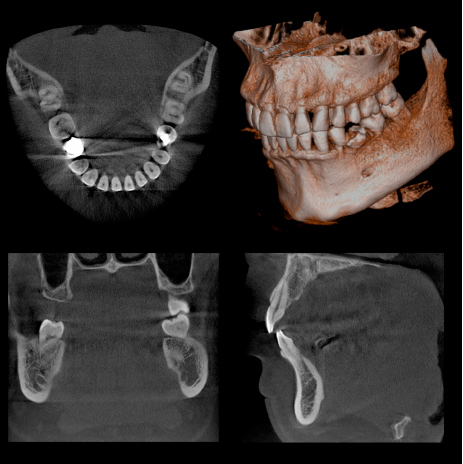

CTスキャンで精密な親知らずの

診断が可能です

歯科用CTを親知らずの抜歯に利用することで、顎骨内にある親知らずの位置を立体的に把握することができます。

これにより、神経を引っ掛けてしまう可能性 や周囲の炎症の程度、病巣の有無や大きさ、位置なども判断・考慮して、治療を行うことができます。

また埋伏歯などの位置なども精密に判断できるので、余分な切開や骨の切削などを避けることができます。